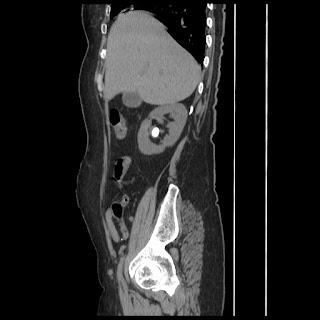

A CT abdomen revealed a left adrenal cortical tumor.

CT images: